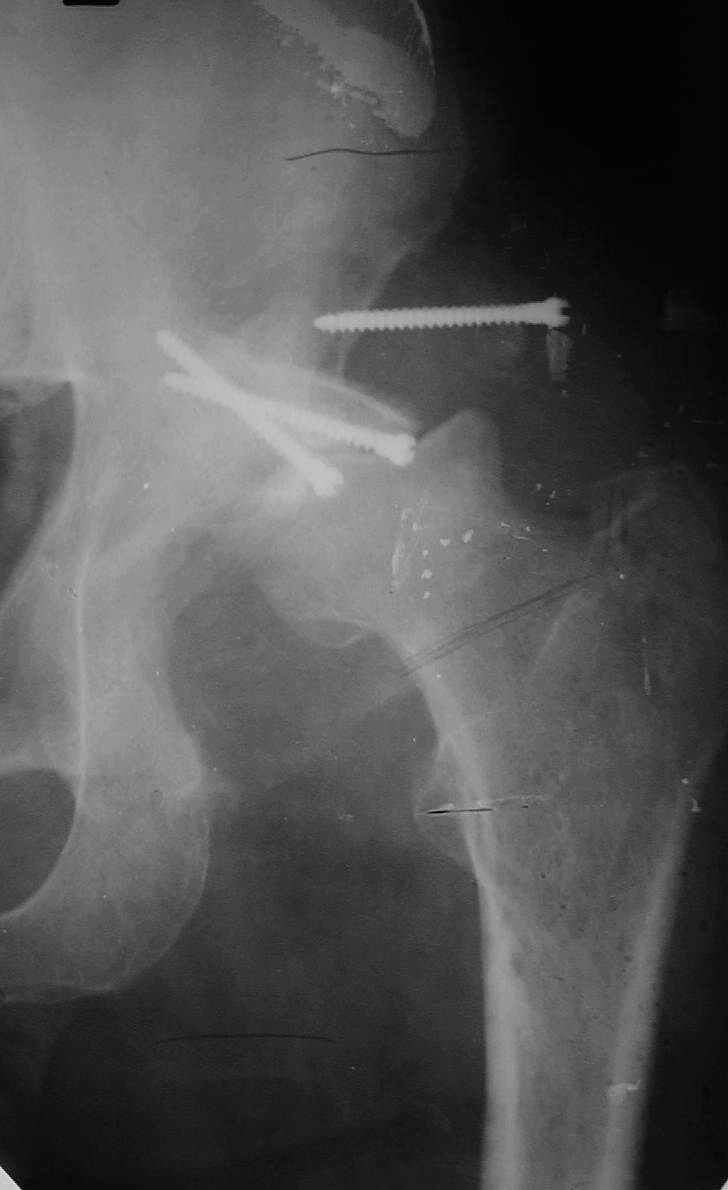

В институте совместно с фирмой Зиммер достаточно регулярно (практически ежемесячно) проводятся 2-х недельные циклы по различным вопросам эндопротезирования. Если есть возможность и желание, мы готовы поделиться с Вами нашим опытом, тем более есть что показать и что обсудить - в настоящее время ежедневно выполняется от 6 до 10 эндопротезирований коленного и тазобедренного сустава. В качестве примеров хочу показать 2 наблюдения, через 1 год и 5 лет после операции

1 год

5 лет